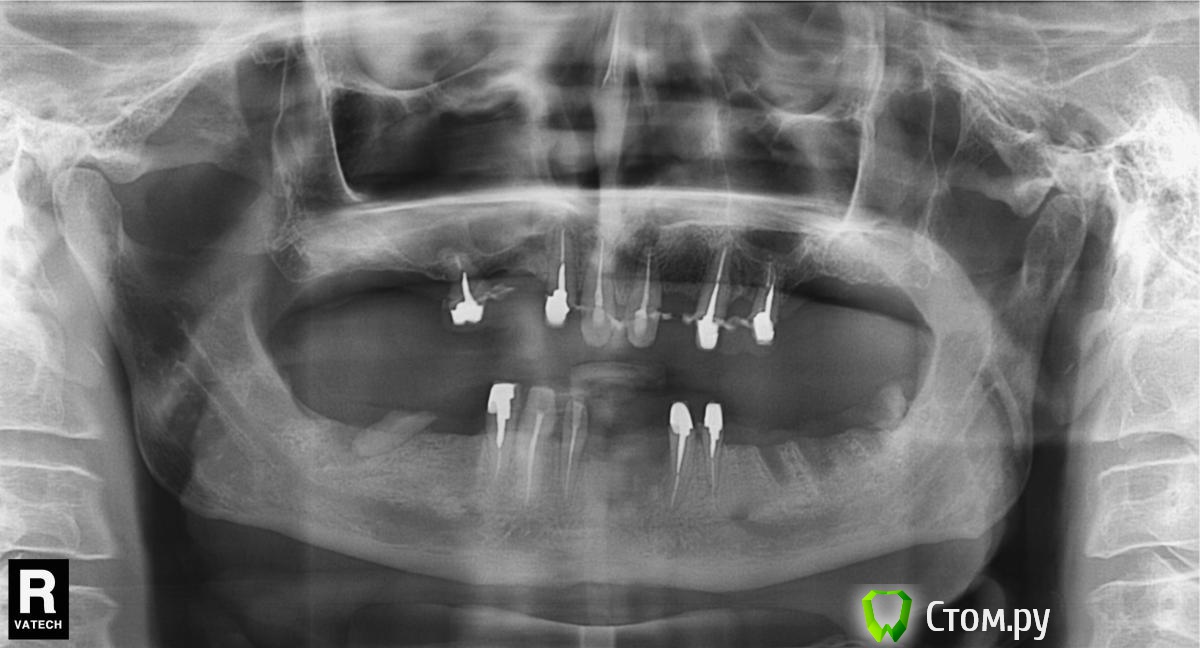

k.t.m. Опубликовано 12 сентября, 2014 Поделиться Опубликовано 12 сентября, 2014 интересует третий сегмент в области ментального отверстия?свой вариант импланты в позицию 6 , 7 и на 5 консоль ,6-12мм7-10ммили взять оба по 10мм? Ссылка на комментарий

Евгений Ходыкин Опубликовано 12 сентября, 2014 Поделиться Опубликовано 12 сентября, 2014 По кт сколько до ментального? Ссылка на комментарий

k.t.m. Опубликовано 12 сентября, 2014 Автор Поделиться Опубликовано 12 сентября, 2014 кт не делал и не буду,исхожу из того что знаю длину 34 зуба без вкладки 14мм-то погрешность около 1мм,по ширене более чем достаточно удалял два месяца назад Ссылка на комментарий

Bier Опубликовано 12 сентября, 2014 Поделиться Опубликовано 12 сентября, 2014 Я вам так скажу, до менталиса там 11-12 мм. 10 мм войдет легко, но если сыкотно, то поставьте 8 мм ) 3 Ссылка на комментарий

max1183 Опубликовано 13 сентября, 2014 Поделиться Опубликовано 13 сентября, 2014 В области мент отверстия 10 поидет пез проблембну а дальше можно 11.5 2 Ссылка на комментарий

red_butler Опубликовано 13 сентября, 2014 Поделиться Опубликовано 13 сентября, 2014 тоже думаю 10 мм пройдет. Если не хотите делать Кт, приготовьте и имплант 8 мм, в ходе операции сделаете снимок с пином параллельности и определитесь с длиной 2 Ссылка на комментарий

k.t.m. Опубликовано 8 декабря, 2014 Автор Поделиться Опубликовано 8 декабря, 2014 (изменено) Подниму тему,пришло время верхних отделов. Вопрос стоит ли наращивать в 2-ем сегменте по вертикали или обойтись синусом и постановкой имплантов,если эстетика не важна для пациента?кто как бы поступил? Изменено 8 декабря, 2014 пользователем k.t.m. Ссылка на комментарий